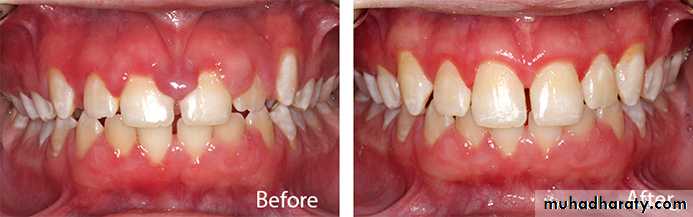

gingivectomy: surgical excision of unattached gingival tissue.gingivoplasty: surgical recountour of the gingival